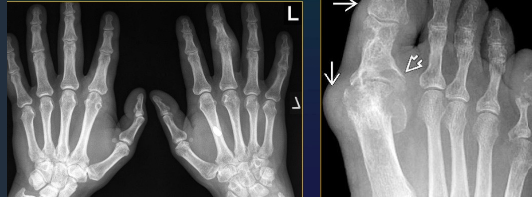

Rheumatoid Arthritis Dg

Rx = business card of RA patients

RA

CharaK RA hands

Focal soft tissue swelling

early=> MCPh, PIPh, ulnar styloid

OP

early=> juxtaarticular, band

late=> diffuse

Erosions

early=> decreased cortical differentiation (dot dash pattern)

marginal = moue ears at basis of the phalanges

subchondral=> pen in cup, destruction of ulna, carpal bones

Cartilage destruction

early false increased of joint space (effusion)

destruction & narrowing of joint space

Subchondral cysts

Malalignement

carpal: ulnar deviation and scaphoid luxation

fingers: MCPh, ulnar deviation, subluxation

RA hand joints

Dg CLUES

Purely erosive

Joint alignement changes

LOC

Classic: symétrie (+ unilateral in early stages)

Early: MCPh, distal RU, RC

Late: PIPh, IC

Almost NEVER involved DIPh

GOUT Imaging recommendations

GOUT Imagistics

Rx (N in first year)

Cartilage destruction (advanced stage)

Tophi

Density, sometimes calcified, eccentric, NOT necessary with neighboring joint changes

RARELY intraosseous calcification

Circumscribed erosions + sclerotic margins

Juxtaarticular, often intraarticular

Gout Dg Clues

Dense tophi, erosiosn

MTPh 1

Lower extremities > up

Small joints > large

Any loc

Oligo, BUT may be polyarticular, asymmetric